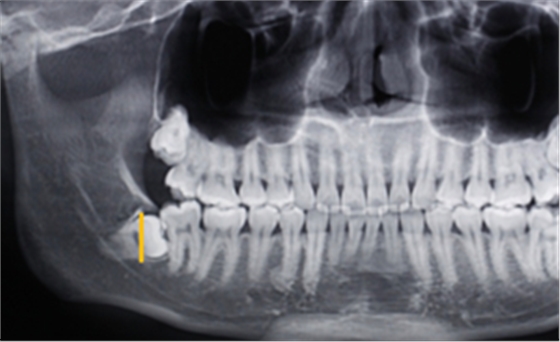

第一:確定阻力去骨的范圍:

第二:充分暴露牙體組織后,沿47牙長軸方向?qū)?8進(jìn)行分冠,分冠線如下: